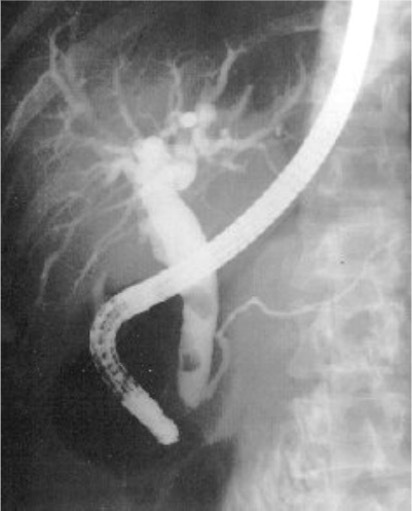

ERCP with stone in common bile duct